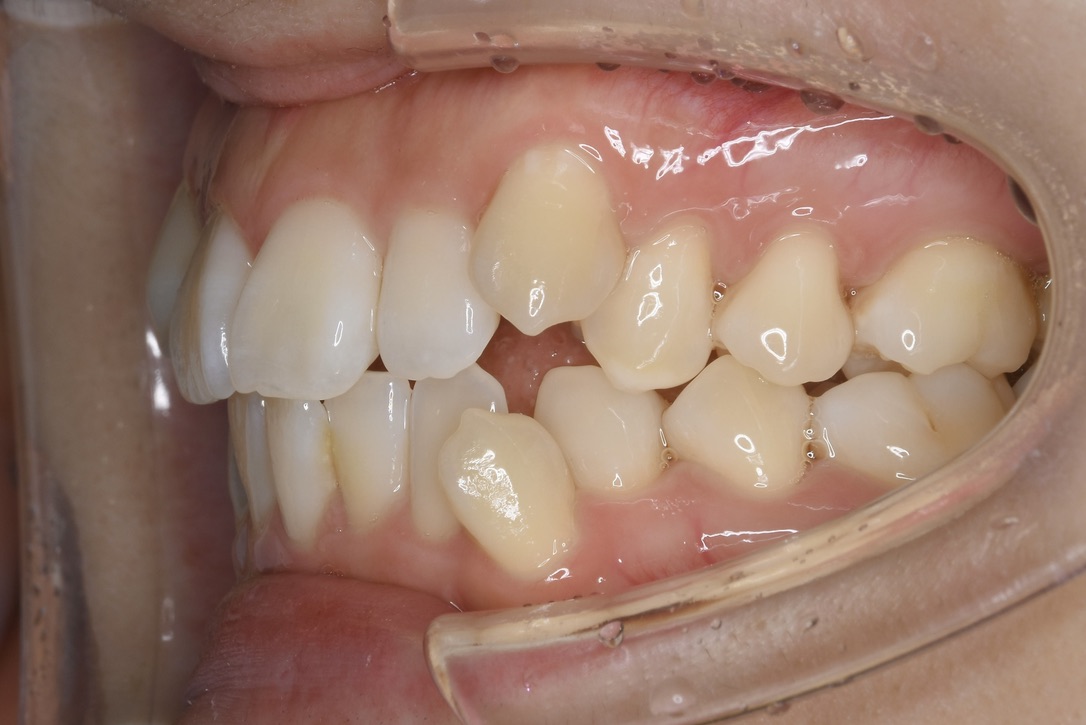

| 主訴 | 上の歯が出ていて、横顔が気になる。 |

|---|---|

| 診断名・主な症状 | 両側第一小臼歯の鋏状咬合を伴う上顎前突 |

| 年齢 | 13歳 |

| 治療内容 | 上下の歯並びの幅を拡げつつ、咬合関係を改善しました。 |

| 使用装置 | 表側矯正(ワイヤー) 矯正用ミニインプラント |

| 抜歯部位 | 抜歯なし |

| 治療期間 | 1年2ヶ月 |

| 通院回数 | 17回 |

| 費用 | 86万円程度(税別) 254 |

| リスク・副作用 | 痛み、歯肉退縮、歯根吸収、抜歯に伴う出血や腫れが生じることがあります。 |